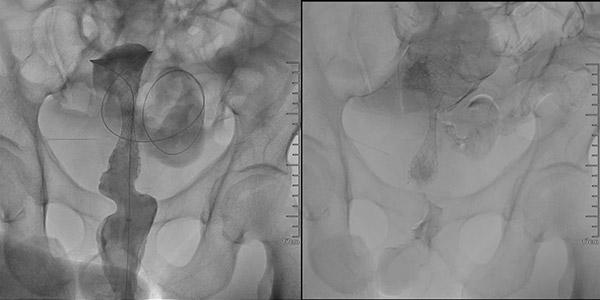

肿瘤介入科张申众主任带领团队,历时三十分钟,在DSA引导下,顺利完成结肠支架置入术。术中利用加硬导丝、导管穿越肠道扭曲狭窄段,确定狭窄部位及长度。选用10F的25mm×9cm的支架,沿着导丝插入支架至狭窄部位。肠道支架调整至合适位置后,在DSA引导下精准释放支架。当支架完整释放后,肠腔瞬间通畅,堵塞的粪便通过支架“喷涌而出”,患者严重的腹痛腹胀症状立刻得到缓解,生命通道被精准打通!

支架释放后肠腔通畅

腹部膨隆的前后对比